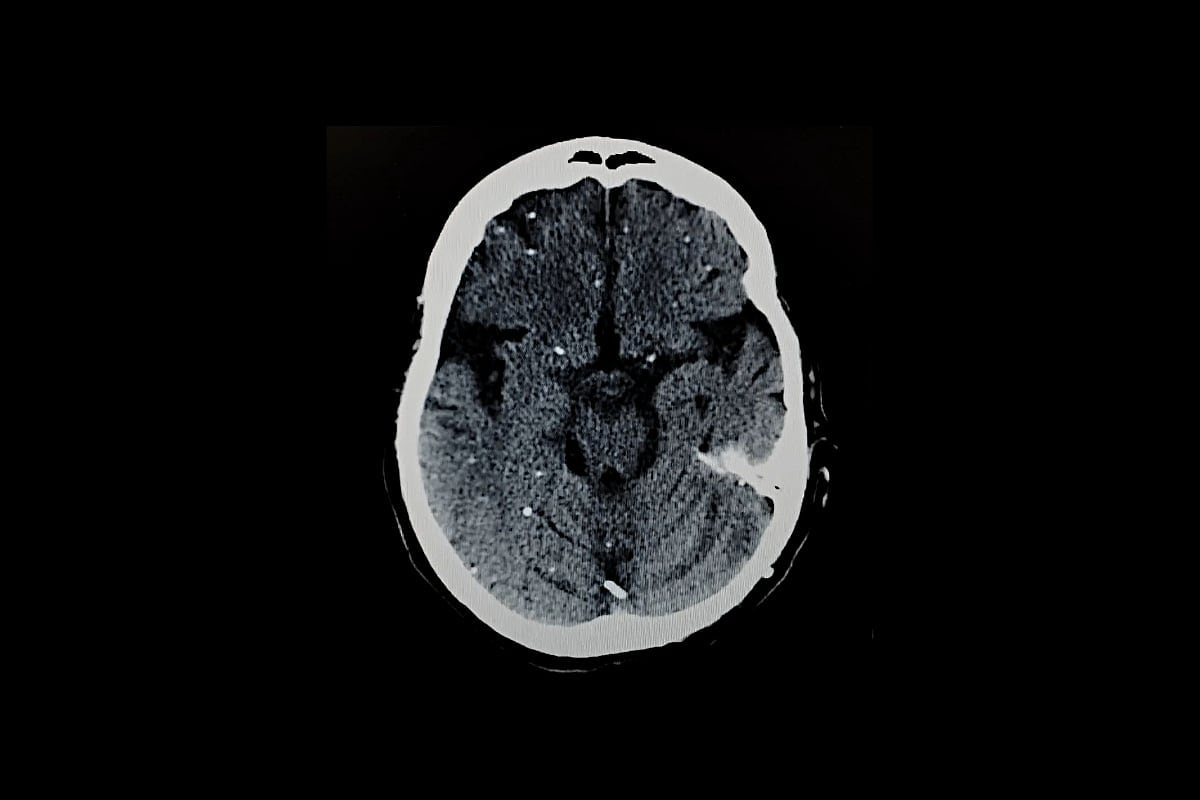

Se protege formando pequeños quistes, principalmente en el cerebro y los músculos. Cada quiste puede albergar cientos de parásitos latentes.

Estos parásitos pueden despertar más tarde, especialmente en personas con sistemas inmunitarios débiles, lo que a veces puede provocar graves problemas cerebrales o oculares. La infección durante el embarazo también puede dañar al feto en desarrollo.

Estos quistes se encuentran con mayor frecuencia en neuronas, células que conforman el sistema nervioso. Pero también aparecen en el corazón y el músculo esquelético, lo que ayuda a explicar por qué las personas pueden infectarse al comer carne poco cocinada.

Estos pueden propagarse por el cuerpo y causar enfermedades graves como daño cerebral (encefalitis toxoplásmica) o pérdida de visión (toxoplasmosis retiniana).